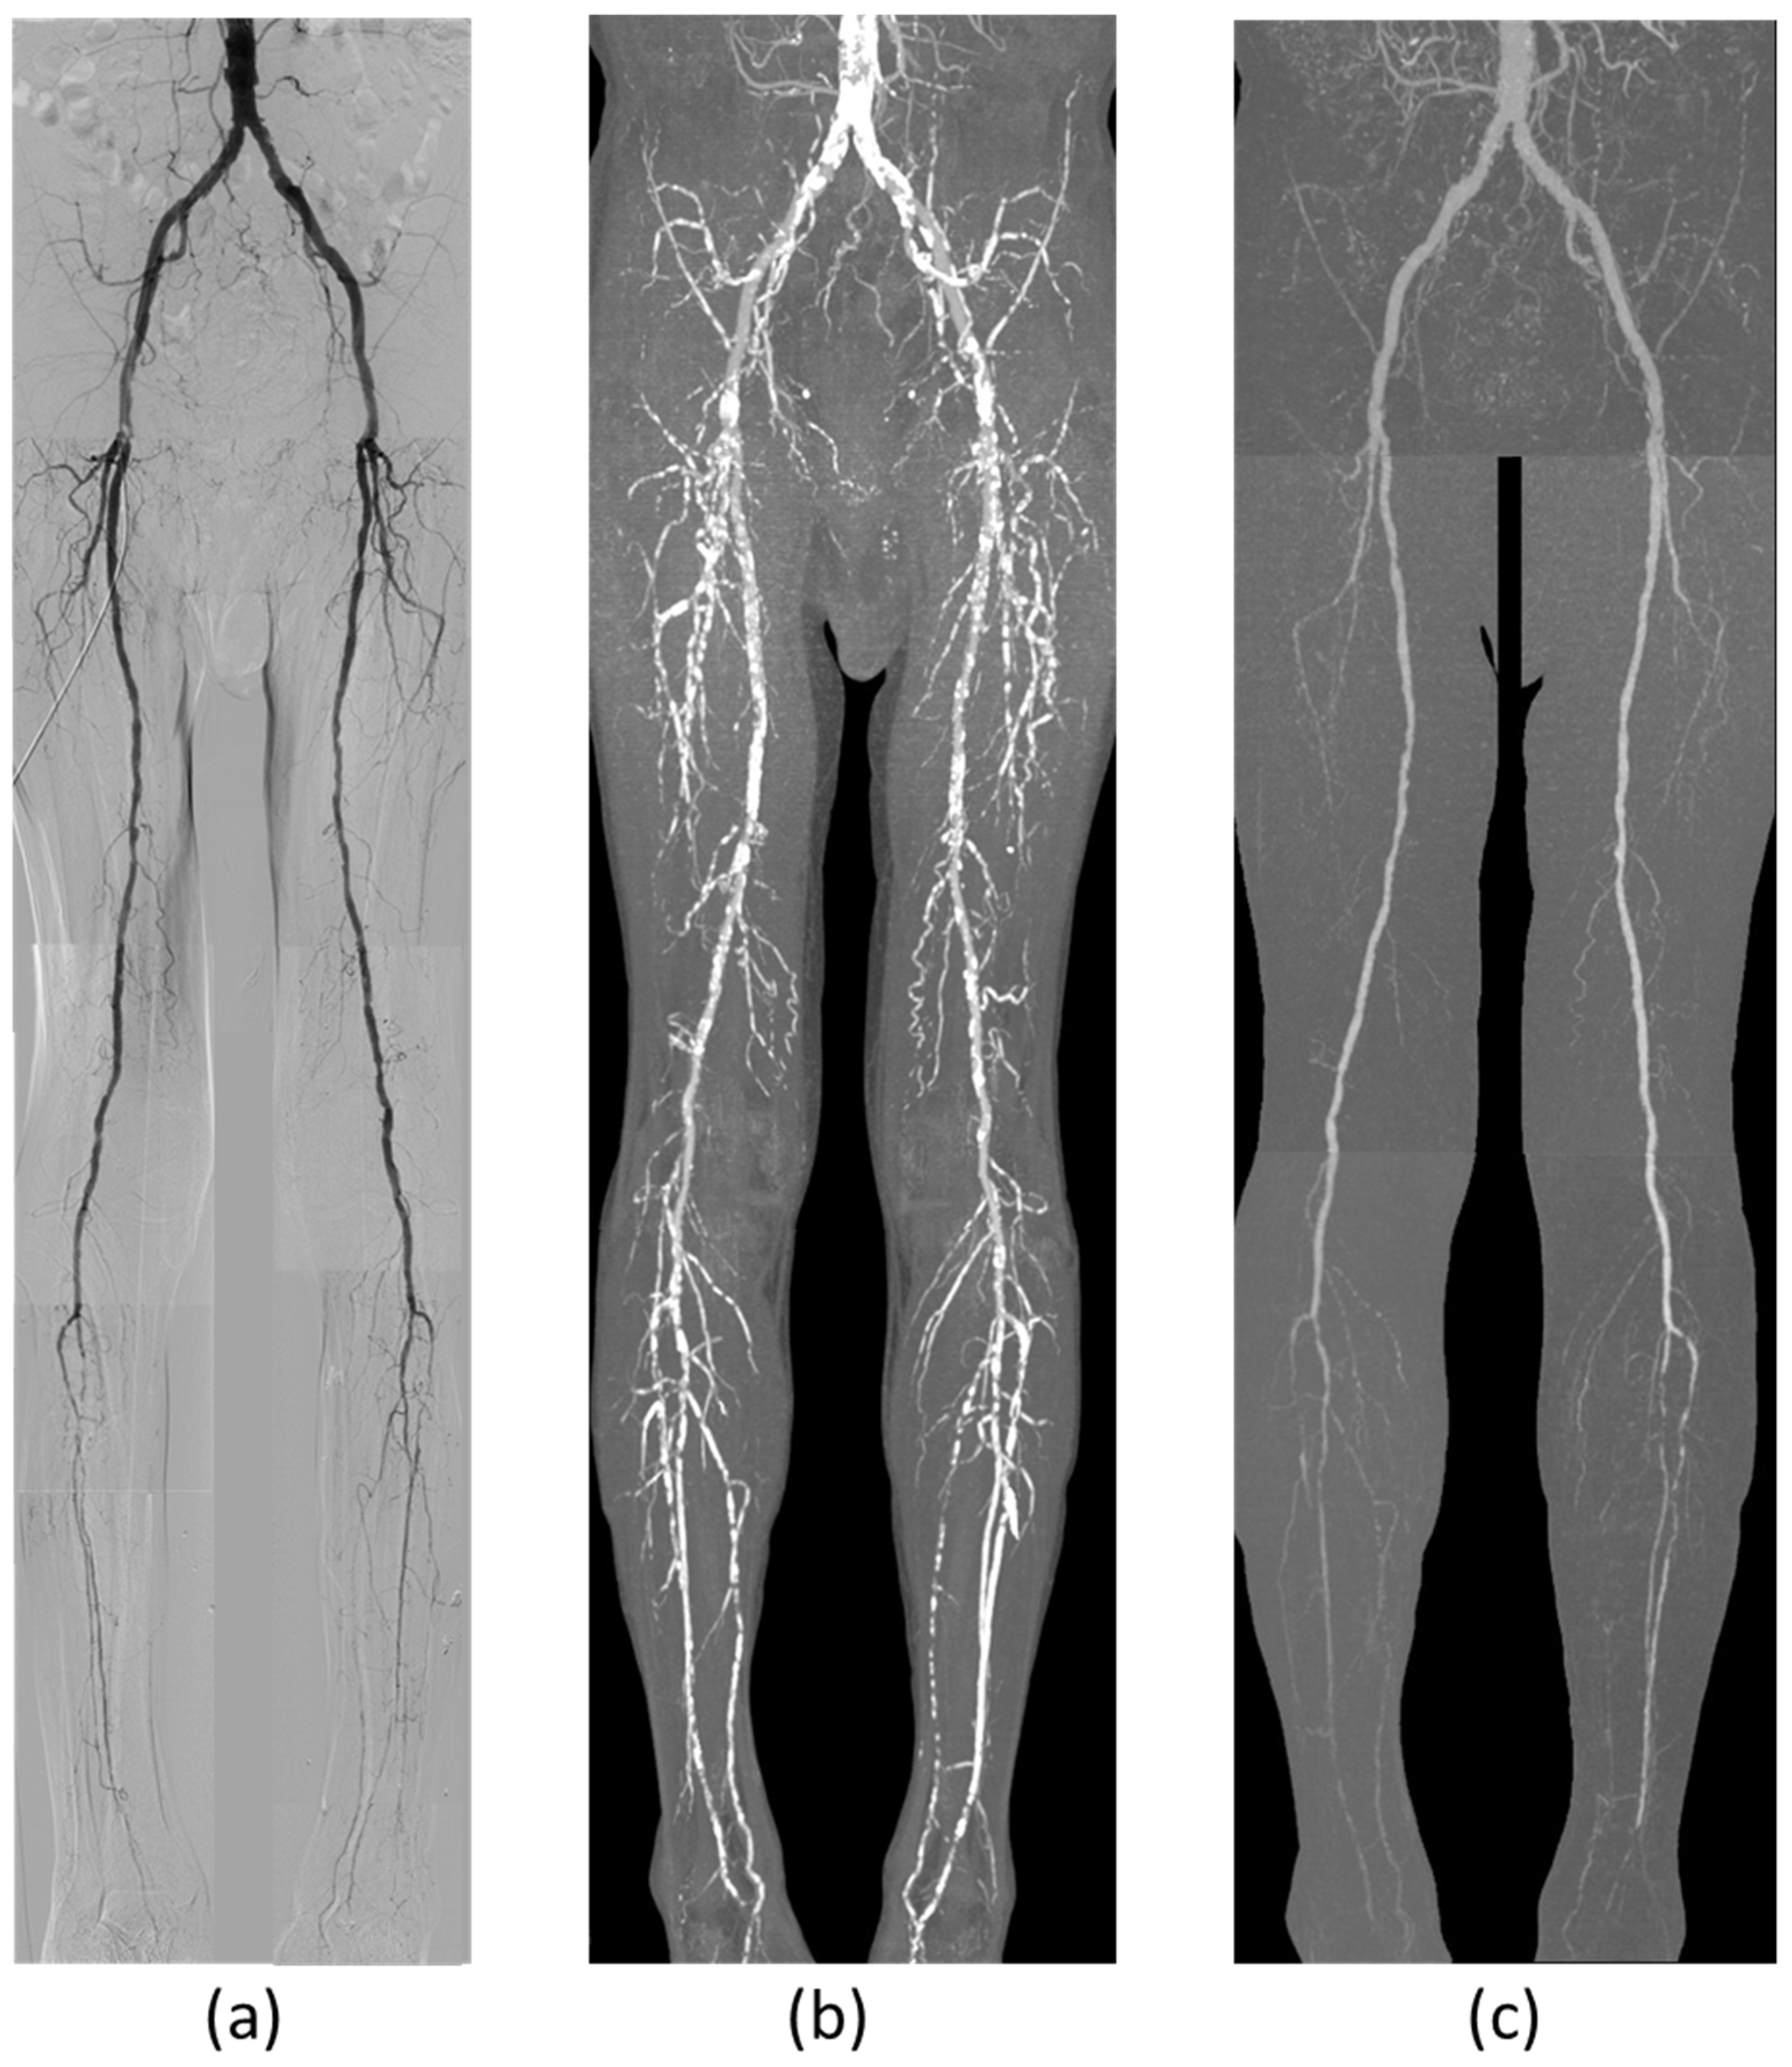

2.2. CT Angiography

2.3. Digital Subtraction Angiography

3. Results

4. Discussion